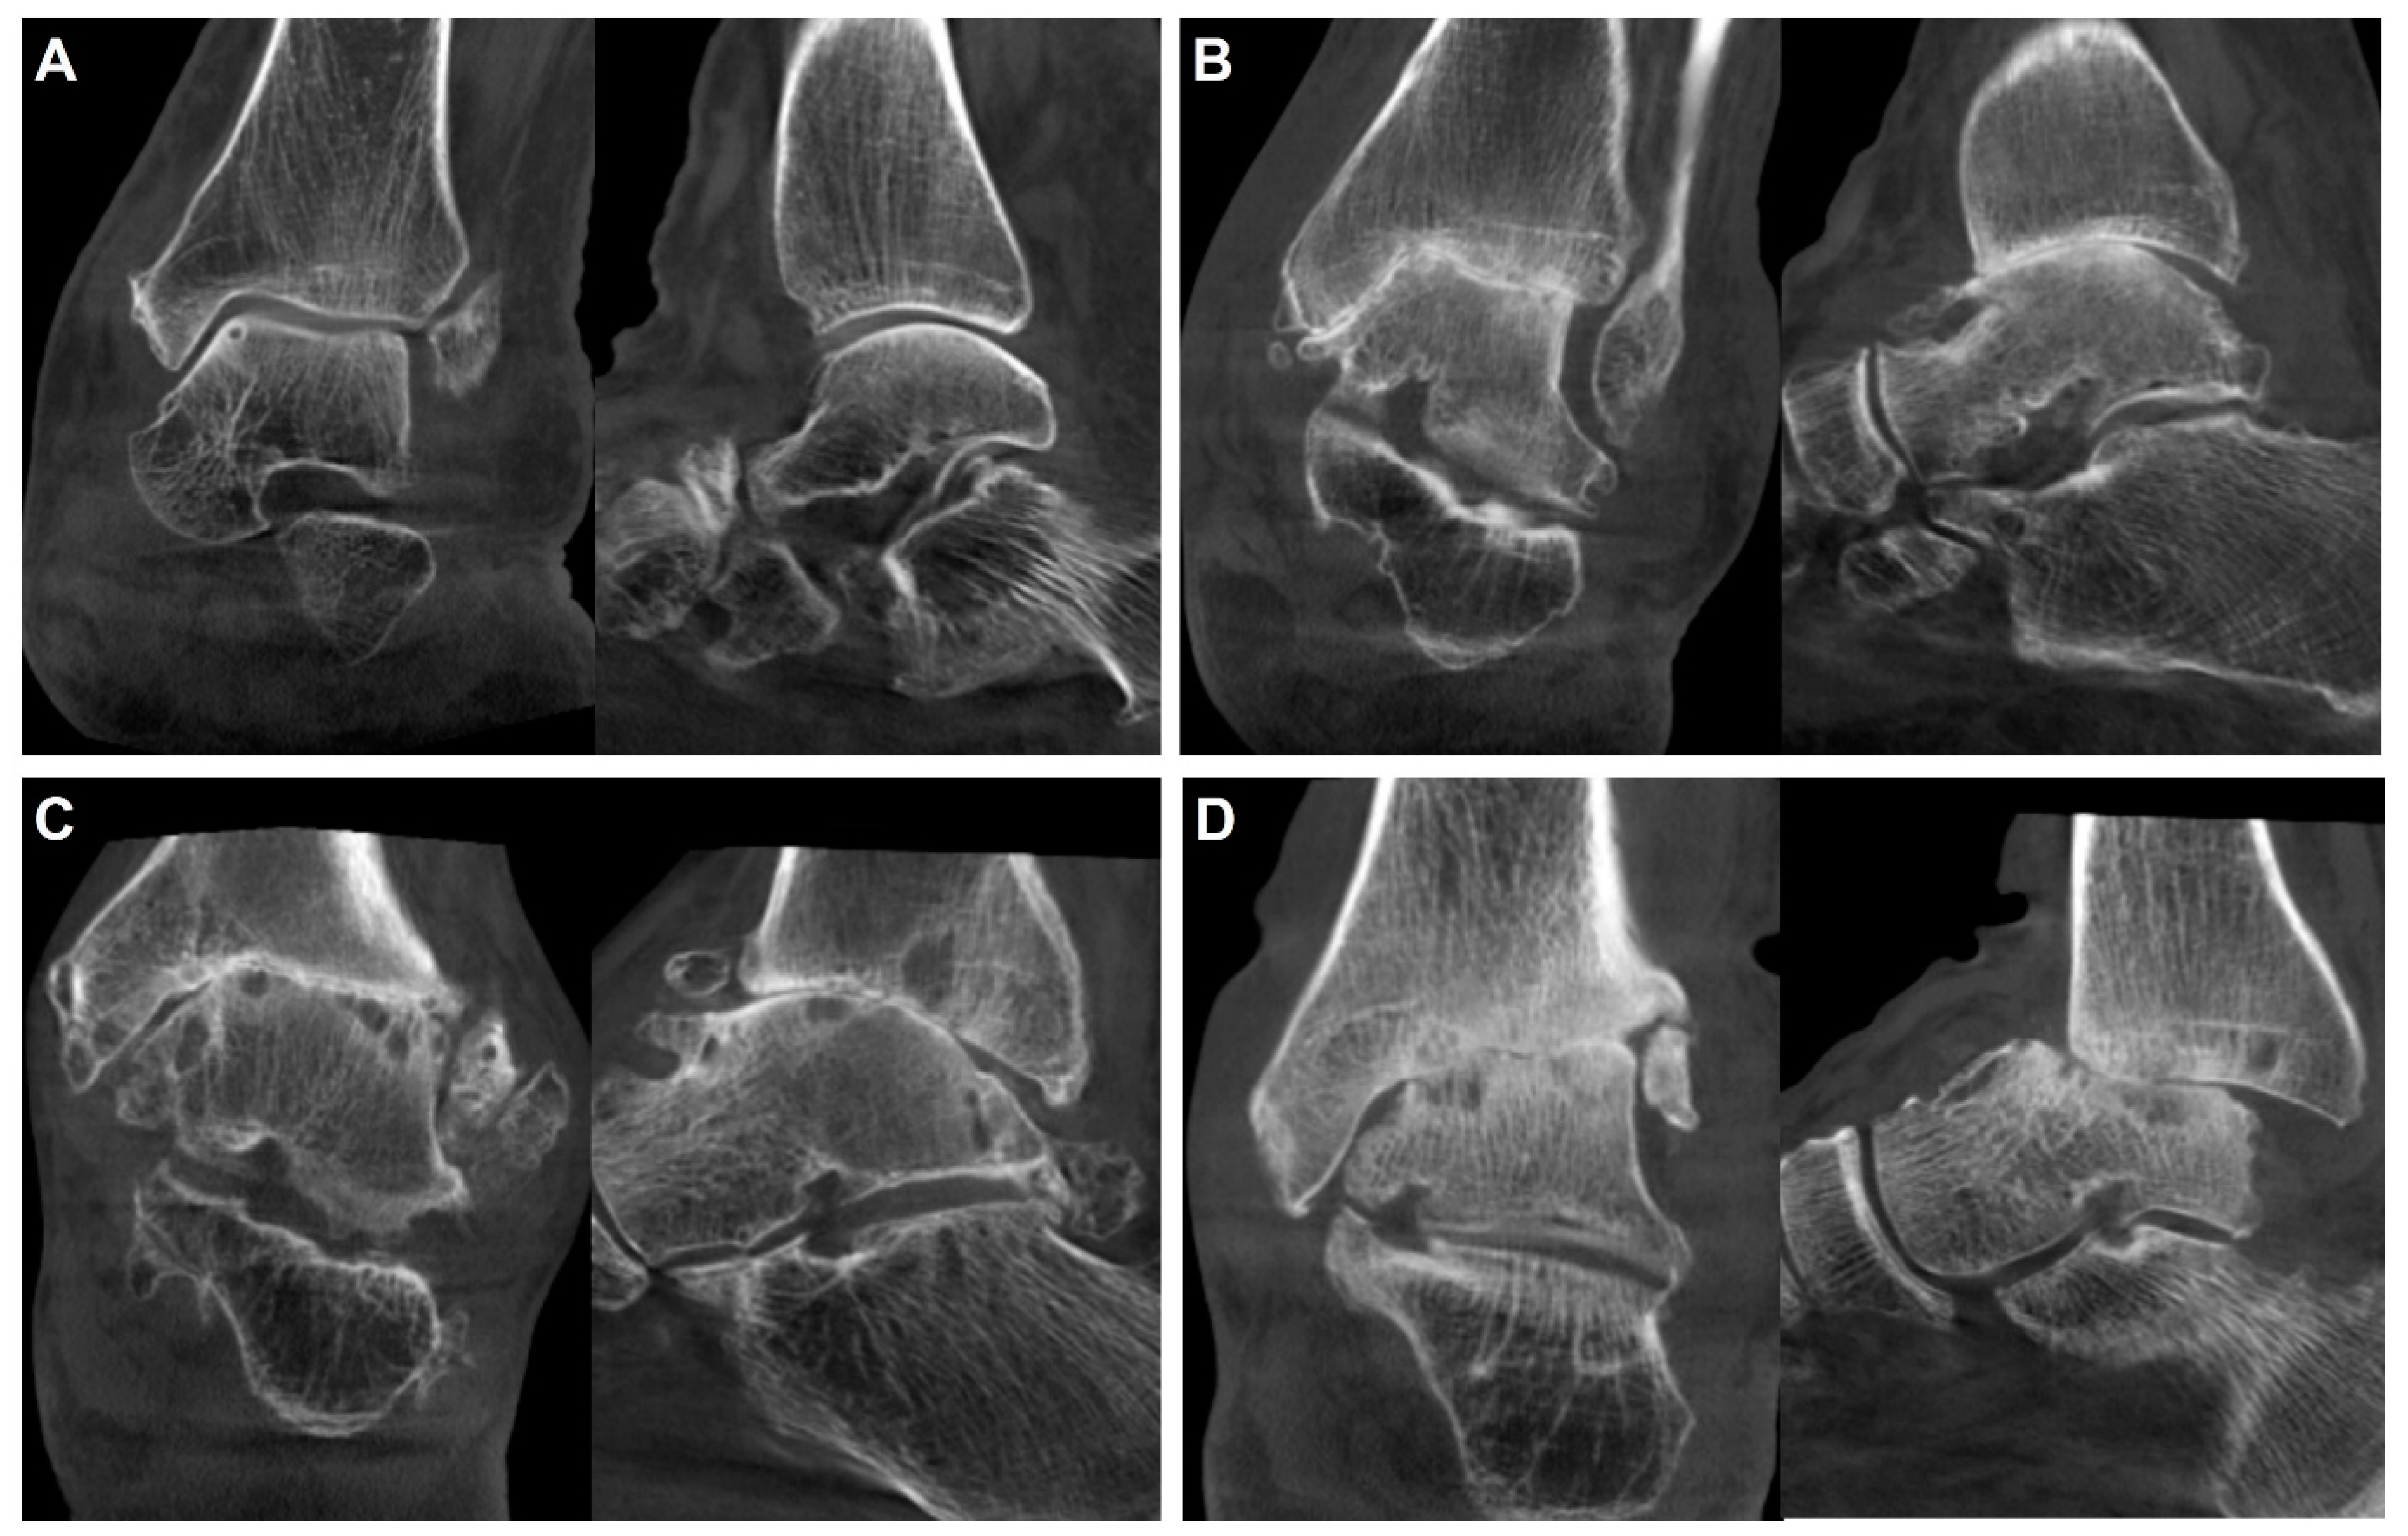

- Lintz, F.; Mast, J.; Bernasconi, A.; Mehdi, N.; de Cesar Netto, C.; Fernando, C.; Buedts, K. 3D, Weightbearing Topographical Study of Periprosthetic Cysts and Alignment in Total Ankle Replacement. Foot Ankle Int. 2020, 41, 1–9. [Google Scholar] [CrossRef] [PubMed]